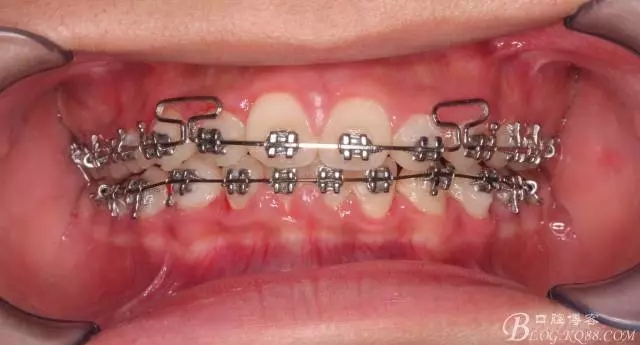

努力沒有白費,中線基本對齊!

一晃快兩年了,我覺得關節(jié)重建及咬合穩(wěn)定,再加上患者的急迫愿望,我們拆除了矯正器。

尖牙關系中性,磨牙關系中性,咬合鎖結(jié)良好!